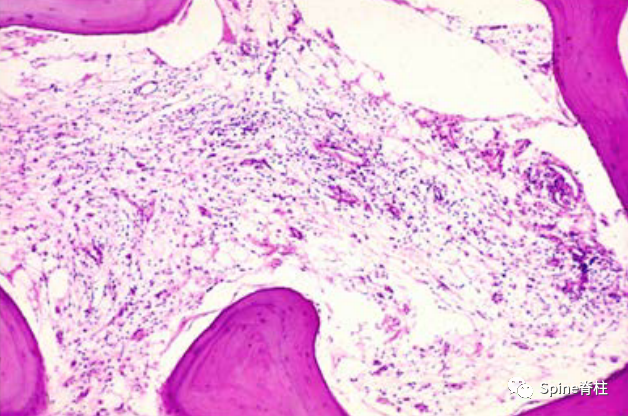

图 1. 终板-椎体交界处的 H&E 染色显示正常组织与椎骨内的造血成分和骨小梁。